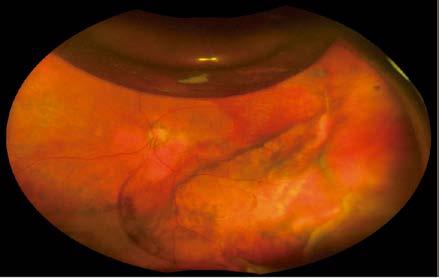

Por los diagnósticos sistémicos encontrados y la lesión coroidea única, se llega a un diagnóstico diferencial de una metástasis coroidea vs una coriorretinopatía exudativa hemorrágica periférica; sin embargo, al no tener la certeza, se decide realizar una vitrectomía diagnóstica 25G. Tras la remoción de la hemorragia vítrea, se observó una masa pigmentada subretiniana en el sector temporal periférico, asociada a desprendimiento exudativo de retina y hemorragia subretiniana (Imagen 3).

Imagen 3